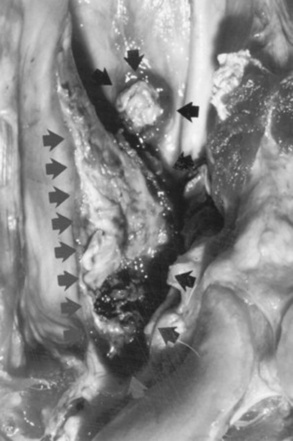

Necropsy Findings

In the acute form of coenurosis, the main finding is coagulation necrosis and inflammation associated with the pathway of the larval form as it migrates through the CNS.1383 This may be visible grossly as yellow to red tracks through the brain parenchyma. Coagulation necrosis and surrounding inflammatory cells, such as degenerate granulocytes, macrophages, and histiocytes, are found microscopically. The mature cysts, up to 7 cm in diameter, are thin walled and contain clear fluid or, occasionally, purulent fluid. Protoscolices, up to many hundreds, can be visualized microscopically within the cysts, which are surrounded by severe and mainly nonsuppurative inflammation. The cysts deform and compress the underlying brain tissue.